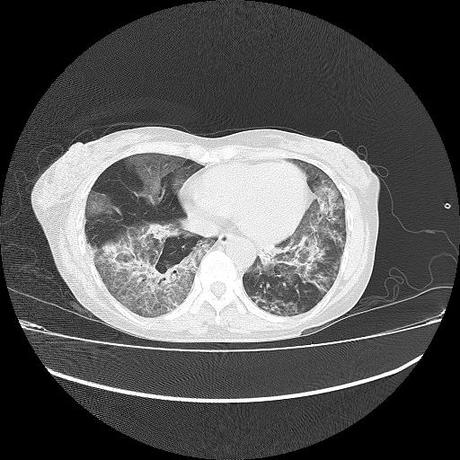

El parénquima pulmonar con areas parcheadas difusas en vidrio despulido combinadas con otras areas hipodensas de baja atenuación debidas a atrapamiento aéreo y engrosamiento intersticial y zonas de fibrosis de predominio en lóbulos medios e inferiores de ambos pulmones.

- LOS HALLAZGOS PUEDEN ESTAR EN RELACIÓN A NEUMOPATIA INTERSTICIAL PROBABLE ETIOLOGIA HIPERSENSITIVA VS AUTOINMUNE/BACTERIANA/FUNGICA.